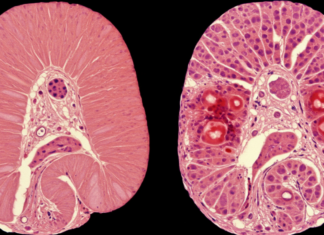

연구팀은 코멧(COMET) 칩 시험을 통해 트라벡테딘 유도 DNA 단절을 측정했다. 각각의 녹색 점은 단일 세포 핵을 나타내며, 핵에서 나오는 꼬리의 길이와 꼬리 내 전체 DNA의 비율은 형성된 단절의 수와 비례한다.

(왼쪽) 자외선(UV) 처리 후, UV에 의한 손상은 뉴클레오타이드 절제 복구(NER)에 의해 DNA에서 제거 및 복구되므로 조금의 단절만 남아있다.

(가운데) 트라벡테딘 처리 후, 중단된 NER 반응으로 인해 DNA 단절이 지속됨을 볼 수 있다. 이러한 단절은 NER에 의존적이며,

(오른쪽) XPF 유전자가 비활성화된 TC-NER 결핍 세포에서는 발생하지 않는다.